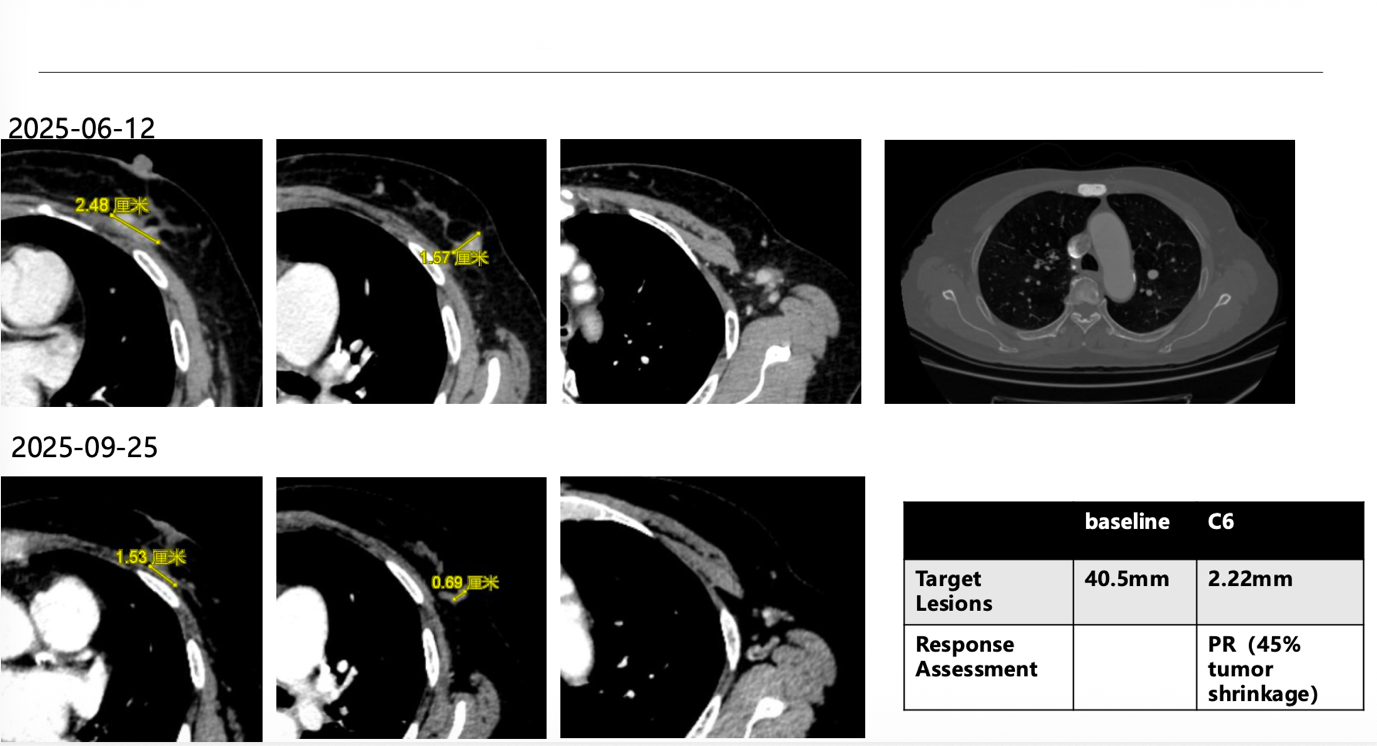

在一线治疗中,患者接受来曲唑联合阿贝西利,影像学评估显示获得部分缓解,并维持了超过1年的疾病控制;在后续进展后,二线接受依维莫司联合依西美坦治疗,但无进展生存期仅约3个月。此后,患者入组一项前瞻性、多中心、单臂II期研究,接受HER2 ADC 治疗6个周期后再次达到部分缓解,靶病灶较基线明显缩小。随后,患者根据研究方案序贯接受达尔西利联合氟维司群治疗,目前仍维持疾病稳定。